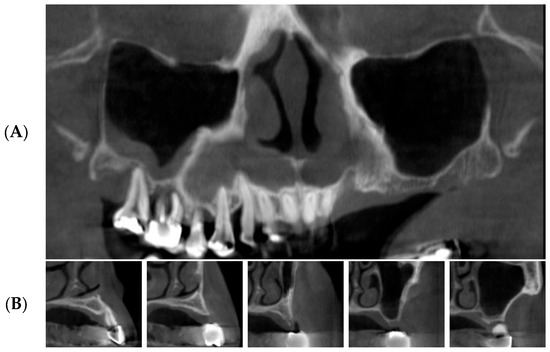

3.2. Radiographic Results